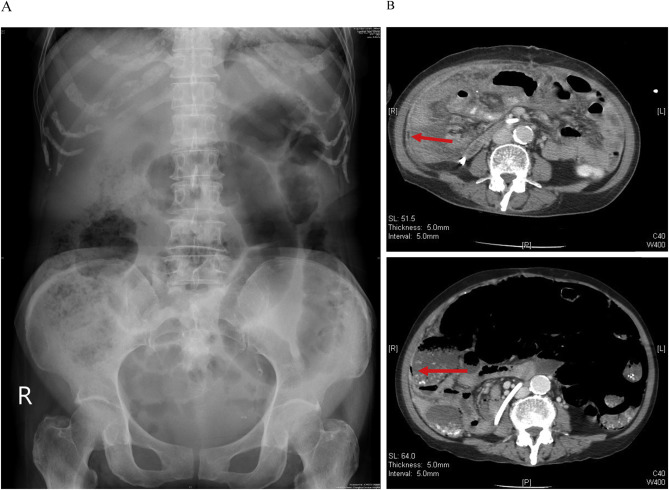

A 79-year-old woman with a history of atrial fibrillation, chronic ischemic heart disease, and chronic renal failure (chronic kidney disease, stage V) complained of abdominal fullness and pain for 1 week prior to hospitalization. The characteristics of her abdominal pain were as follows: located at the umbilical area, 1–2 hours in duration, an onset-to-maximal intensity interval of seconds, a frequency of 2–3 times/day, aggravated by feeding, and relieved by rest. The abdominal pain became more severe and frequent with additional nausea and vomiting, and fever developed 1 day before hospitalization. Subsequently, she was brought to the emergency department (ED) of our institute for help. At the ED, vital-sign measurements were: blood pressure, 100/90 mmHg; temperature, 37°C; pulse rate, 110 beats/min; and respiratory rate, 20 breaths/min. The patient appeared acutely ill, and the abdomen was distended and ovoid. There was radiation pain and tenderness to her back, and abdominal fullness over the right quadrant area (negative Murphys sign), but no rebounding pain. Initial laboratory data at the ED showed a white blood cell count of 2900/μL, with 68.1% neutrophils, 8.7 g/dL hemoglobin level, 97,000/μL platelet count, 19.8 s prothrombin time with an international normalized ratio of 1.84, 140 mm/h erythrocyte sedimentation rate (ESR), 7.1 mg/dL C-reactive protein level, 73 U/L serum amylase level, 2.56 mg/dL total bilirubin level, 156 U/L glutamic-pyruvic transaminase level, 94 μg/dL ammonia level, 55 mg/dL urea nitrogen level, and 6.13 mg/dL serum creatinine level. A kidney, ureter, and bladder (KUB) X-ray showed excessive bowel gas retention and no free air (Figure 1 A). Abdominal ultrasound (US) revealed small ascites, a minute liver cyst, and small calcification spots in S8. Her initial chest film revealed no definite active lung lesion. The patient was admitted under a tentative diagnosis of intestinal obstruction. Nulla per os and fluid hydration were administered immediately, and the acuity and progress of the intestinal obstruction were monitored. Acute-on-chronic renal failure and lung edema developed after fluid hydration, and the patient was transferred to the intensive care unit (ICU) due to respiratory failure. Ceftriaxone (2000 mg/day) plus azithromycin and furosemide for 3 days was prescribed for possible pneumonia and pulmonary edema during this period. Coma and tremor due to uremic encephalopathy were noted, and hemodialysis was performed due to possible uremic encephalopathy. Serial follow-up KUB showed excessive bowel gas retention without significant dilatation of the bowel loops, and colonoscopy (up to the cecum) revealed internal hemorrhoids and redundant colon. Laxatives, neostigmine (0.25 mg intramuscular injection once daily) and oral erythromycin (250 mg four times daily) were prescribed. Fever, tachypnea, and hypoxemia developed, and follow-up CT showed air collection in the bowel wall from the jejunum to the ascending colon without obstructive level ( Figure 1 B). Laparoscopic surgery was performed, and the findings revealed multiple whitish nodules covering the peritoneum. Pathological analysis of the peritoneal nodules revealed caseating granulomatous inflammation. TBP was suspected, and an anti-tuberculosis regimen, including Rifinah 300/150 (Peili, Taichung, Taiwan; 300 mg/day rifampicin plus 150 mg/day isoniazid), ethambutol (Peili, Taichung, Taiwan; 800 mg three times per week), and pyrazinamide (Peili; 1200 mg three times per week), and a modified HERZ regimen (rifampicin + isoniazid + ethambutol + pyrazinamide) were empirically initiated according to guidelines for TB treatment [4] . The condition of the patient stabilized and she was transferred to a ward after a 2-week ICU stay. The modified HERZ regimen was continued after ascitic fluid and tissue cultures were positive for Mycobacterium tuberculosis 1 month later. The total duration of the modified HERZ regimen was 12 months, and the patient recovered fully.

Images of the patient consistent with tuberculous peritonitis. (A) Kidney, ...

Figure 1.

Images of the patient consistent with tuberculous peritonitis. (A) Kidney, ureter, and bladder X-ray showing increased bowel gas. (B) Computed tomography indicating thickened peritoneum with mild ascites and air collection (arrow) in the bowel wall from the jejunum to the ascending colon and suspected pneumatosis intestinalis.